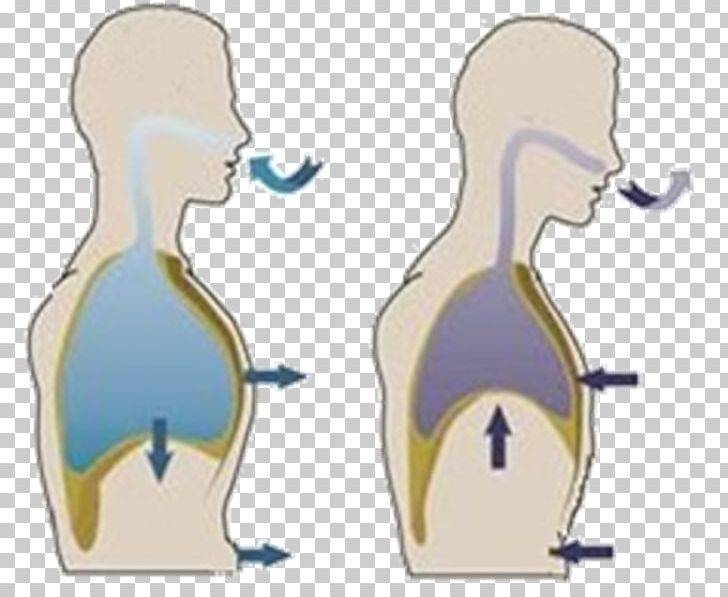

Самый эффективный способ дышать — это “опускать воздух вниз, к животу”. Когда диафрагма опускается вниз, живот расширяется, чтобы наполнить легкие воздухом.

“Дыхание животом” эффективно, поскольку тянет легкие вниз, создавая отрицательное давление внутри грудной клетки. Это приводит к поступлению воздуха в легкие.

Все виды дыхания разделяются на три типа:

- Поверхностное, или ключичное, когда в процессе дыхания двигаются плечи, а рёбра выступают вперёд. В дыхании задействованы только верхние отделы лёгких, в организм попадает очень мало кислорода. Ключичное дыхание часто свойственно пожилым людям, курильщикам и тем, кто ведёт малоподвижный образ жизни.

- Среднее грудное (межрёберное), когда при дыхании расширяется и поднимается грудная клетка, а живот и ключицы не двигаются. В процессе задействованы средние отделы лёгких. Конечно, это лучше, чем поверхностное дыхание, но брюшные мышцы всё равно остаются ограниченными в движении. Это наиболее распространённый способ дыхания среди людей средних лет.

- Диафрагмальное (брюшное), когда в момент вдоха живот выступает вперёд, а на выдохе подтягивается по направлению к позвоночнику.

Главный орган в брюшном дыхании — диафрагма. Диафрагмальная мышца — это куполообразная перегородка, она отделяет грудную клетку от органов, расположенных ниже в брюшной полости. На вдохе диафрагмальная мышца идёт вниз и сжимается, заставляя брюшную стенку выдвигаться вперёд. В момент выдоха диафрагмальная мышца возвращается вверх и приобретает форму купола, выгоняя воздух из лёгких.

Что такое дыхание?

Дыхание – это физиологический процесс, который обеспечивает человеческий организм кислородом, необходимым для функционирования всех органов и тканей. Чем глубже вдох, тем больше кислорода поступает в организм и тем быстрее клетки им насыщаются. Второй неотъемлемой частью дыхания является выдох, при котором организм освобождается от углекислого газа, являющимся побочным продуктом насыщения клеток кислородом. Чем более эффективным будет выдох, тем больше отравляющего организм углекислого газа его покинет.

Среди всех типов дыхания у человека естественным считается именно брюшное. Также его называют абдоминальным и диафрагмальным. Считается, что такая техника приносит больше пользы, чем все остальные, поскольку именно при ней оказывается положительное воздействие на весь организм: тело очищается от шлаков и токсинов, а за счет работы диафрагмальной перегородки происходит непроизвольный массаж органов брюшной полости.

Теперь осталось разобраться в том, как правильно дышать – животом или грудной клеткой. Вне зависимости от того, делается вдох носом или ртом, в этом процессе задействуется торс. Большинство людей склонны думать, что правильнее дышать грудью, хотя это мнение не является верным. Такая техника позволяет дышать поверхностно, поскольку при ней не задействуются все легочные альвеолы. К тому же само по себе грудное дыхание подразумевает короткие вдохи и выдохи.